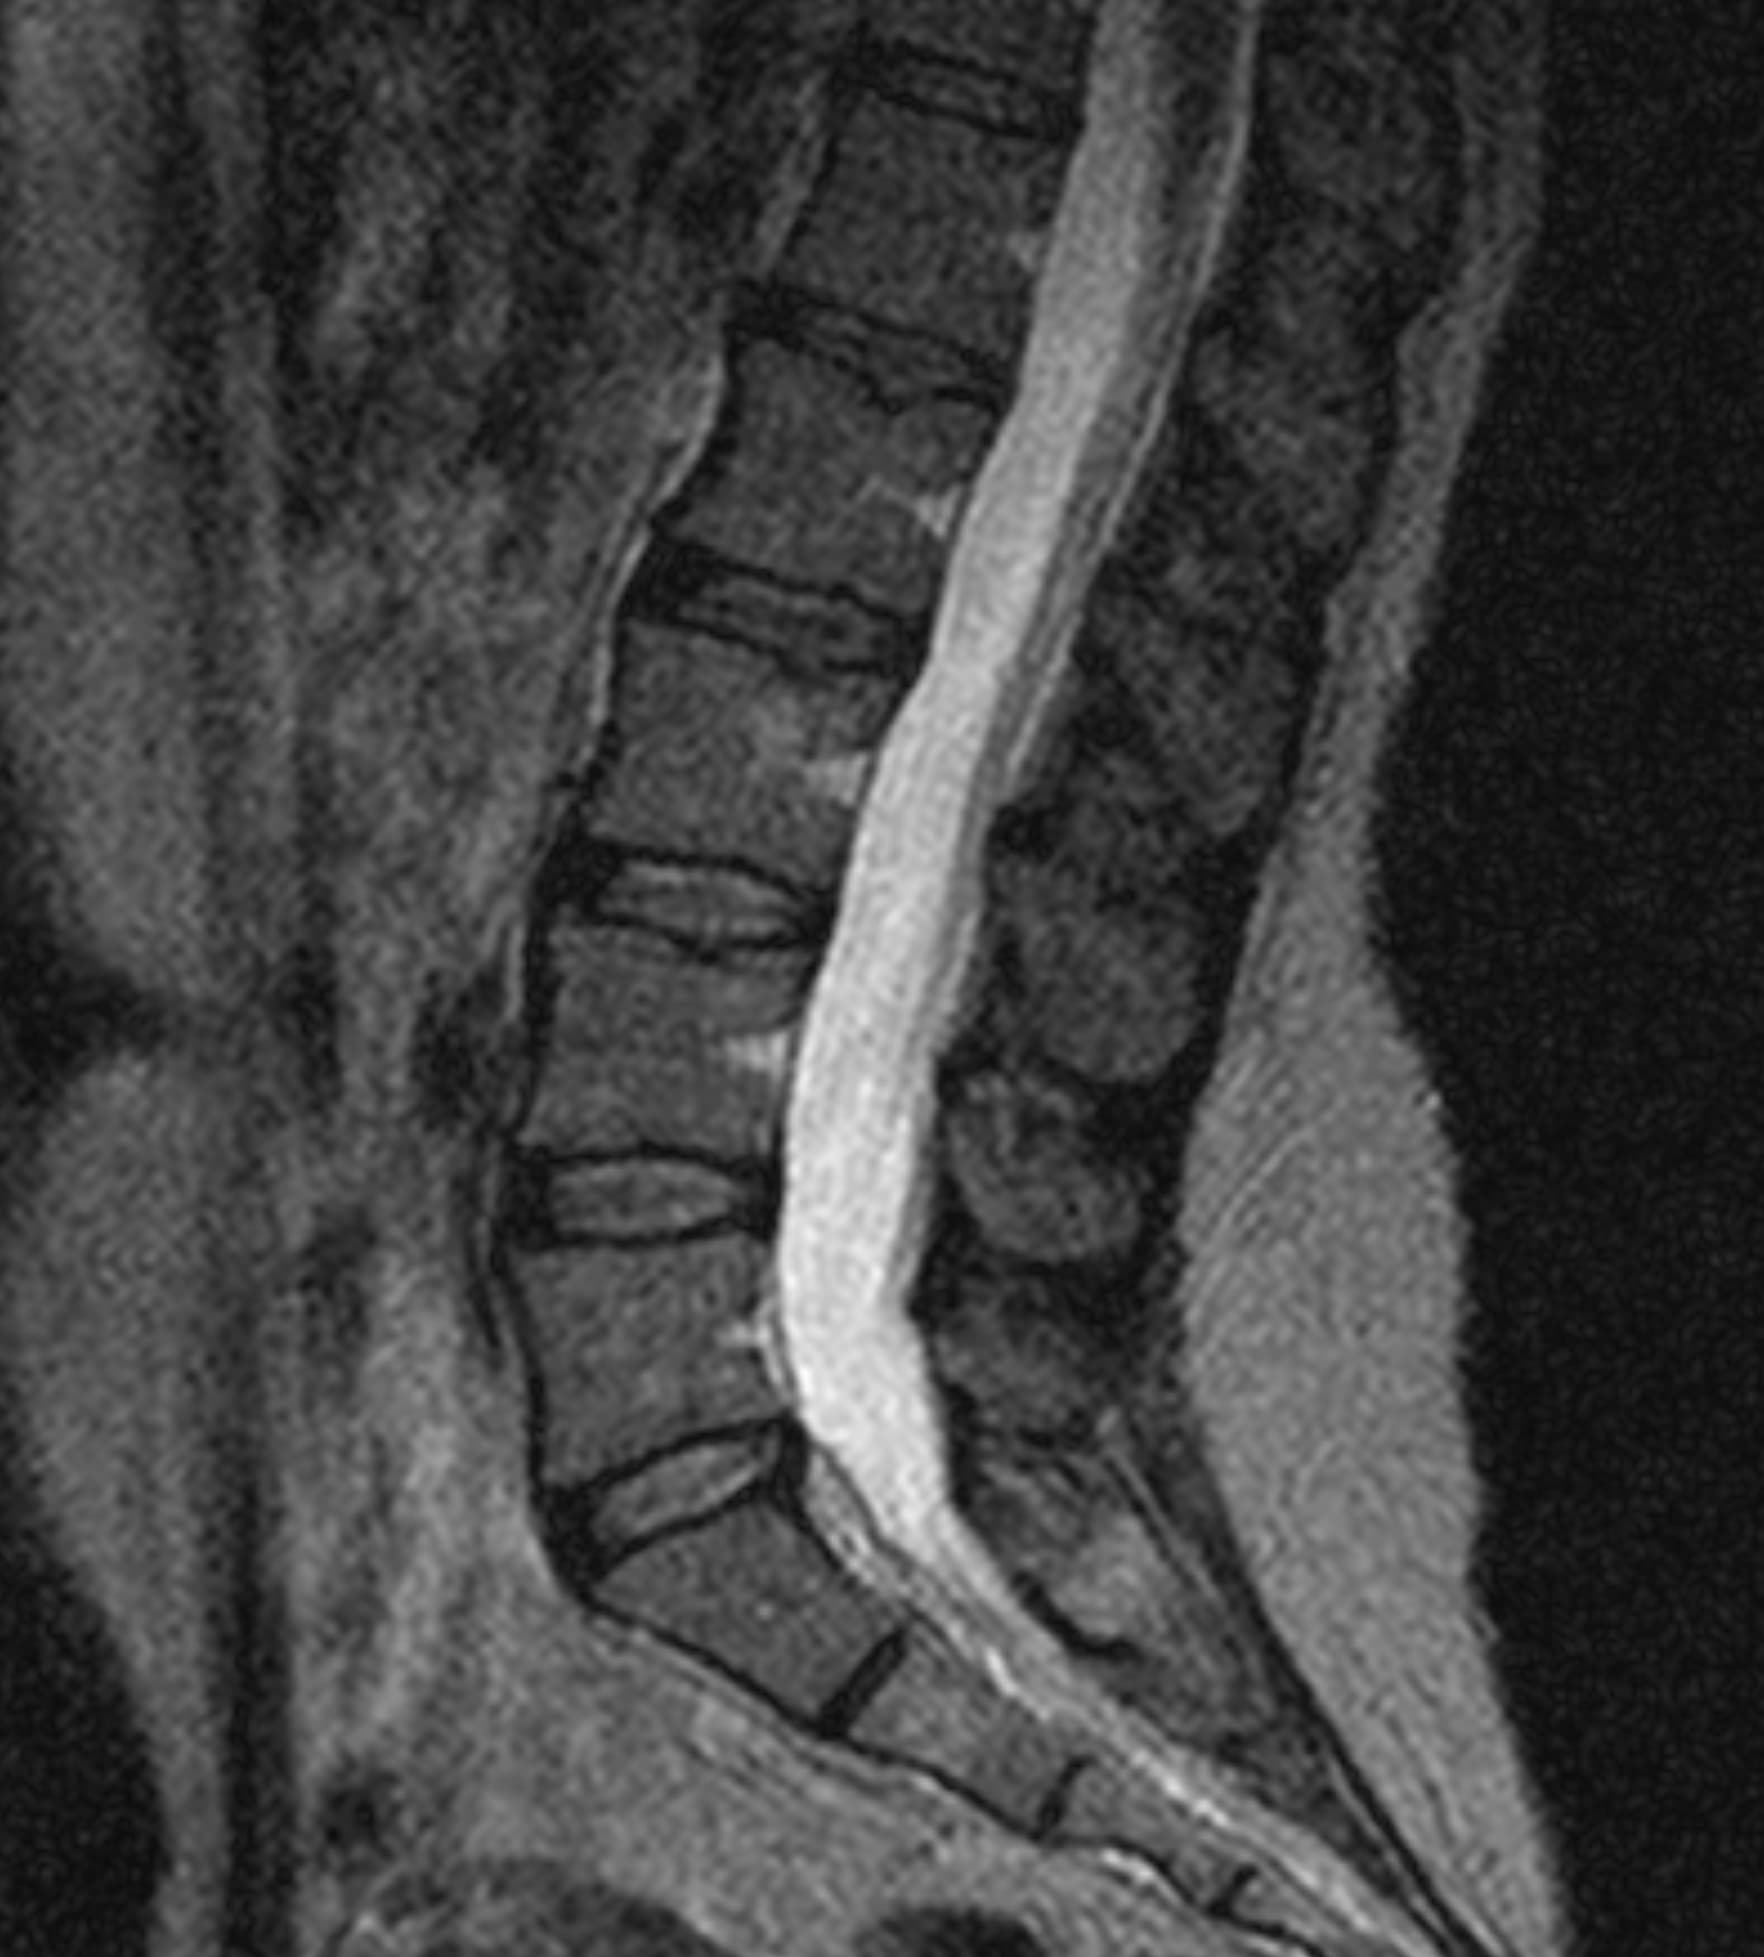

Δείτε πραγματικά παραδείγματα του SwiftMR™ σε διάφορα συστήματα MRI και ανατομικές περιοχές

Scan time 03:08

Scan time 1:12